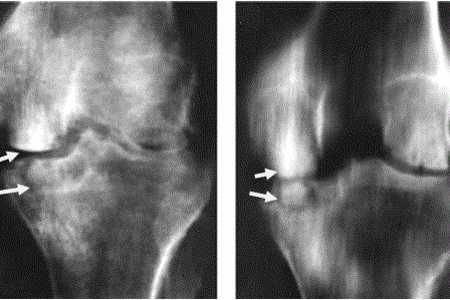

Для подтверждения диагноза назначают рентгенографию грудной клетки, рентгенографию пораженного сегмента и МРТ пораженного сегмента. На снимках грудной клетки больных, страдающих туберкулезом костей, выявляются кальцинированные первичные туберкулезные очаги в верхних отделах легких и внутригрудных лимфатических узлах. На рентгенограммах позвоночника или пораженных костей конечностей видны очаги разрушения и секвестры. В некоторых случаях удается заметить тени натечных абсцессов.

Признаки болезни можно увидеть на рентгеновских снимках. Между суставами появляются расстояния, изменяется костная структура, поверхность хрящей становится неровной, в кости появляются полости. Пораженные суставы можно определить по наличию припухлостей тканей или их атрофии.

На рентгенограммах можно рассмотреть сужение щели сустава, неровности хрящевых поверхностей, размытые очертания пораженной кости, образования в суставной полости. Если есть абсцесс, то он обнаруживается в виде тени возе туберкулезного очага.

При просмотре снимков в динамике в активную фазу можно обнаружить увеличение патологического очага, сужение или полное исчезновение суставных щелей, разрушение трабекул, полостные образования с белковым содержимым или с вкраплениями. По мере прогрессирования патологии поражается соседняя костная ткань.

Если на рентгенограмме костей видны вкрапления, рисунок носит пестрый характер, то это говорит о том, что процесс находится в активной фазе, в дальнейшем могут возникать рецидивы процесса.

В фазе затухания на рентгенограмме видны восстановленные трабекулы, четкое очертание кости, признаки атрофических костных явлений и остеопороз уменьшаются.